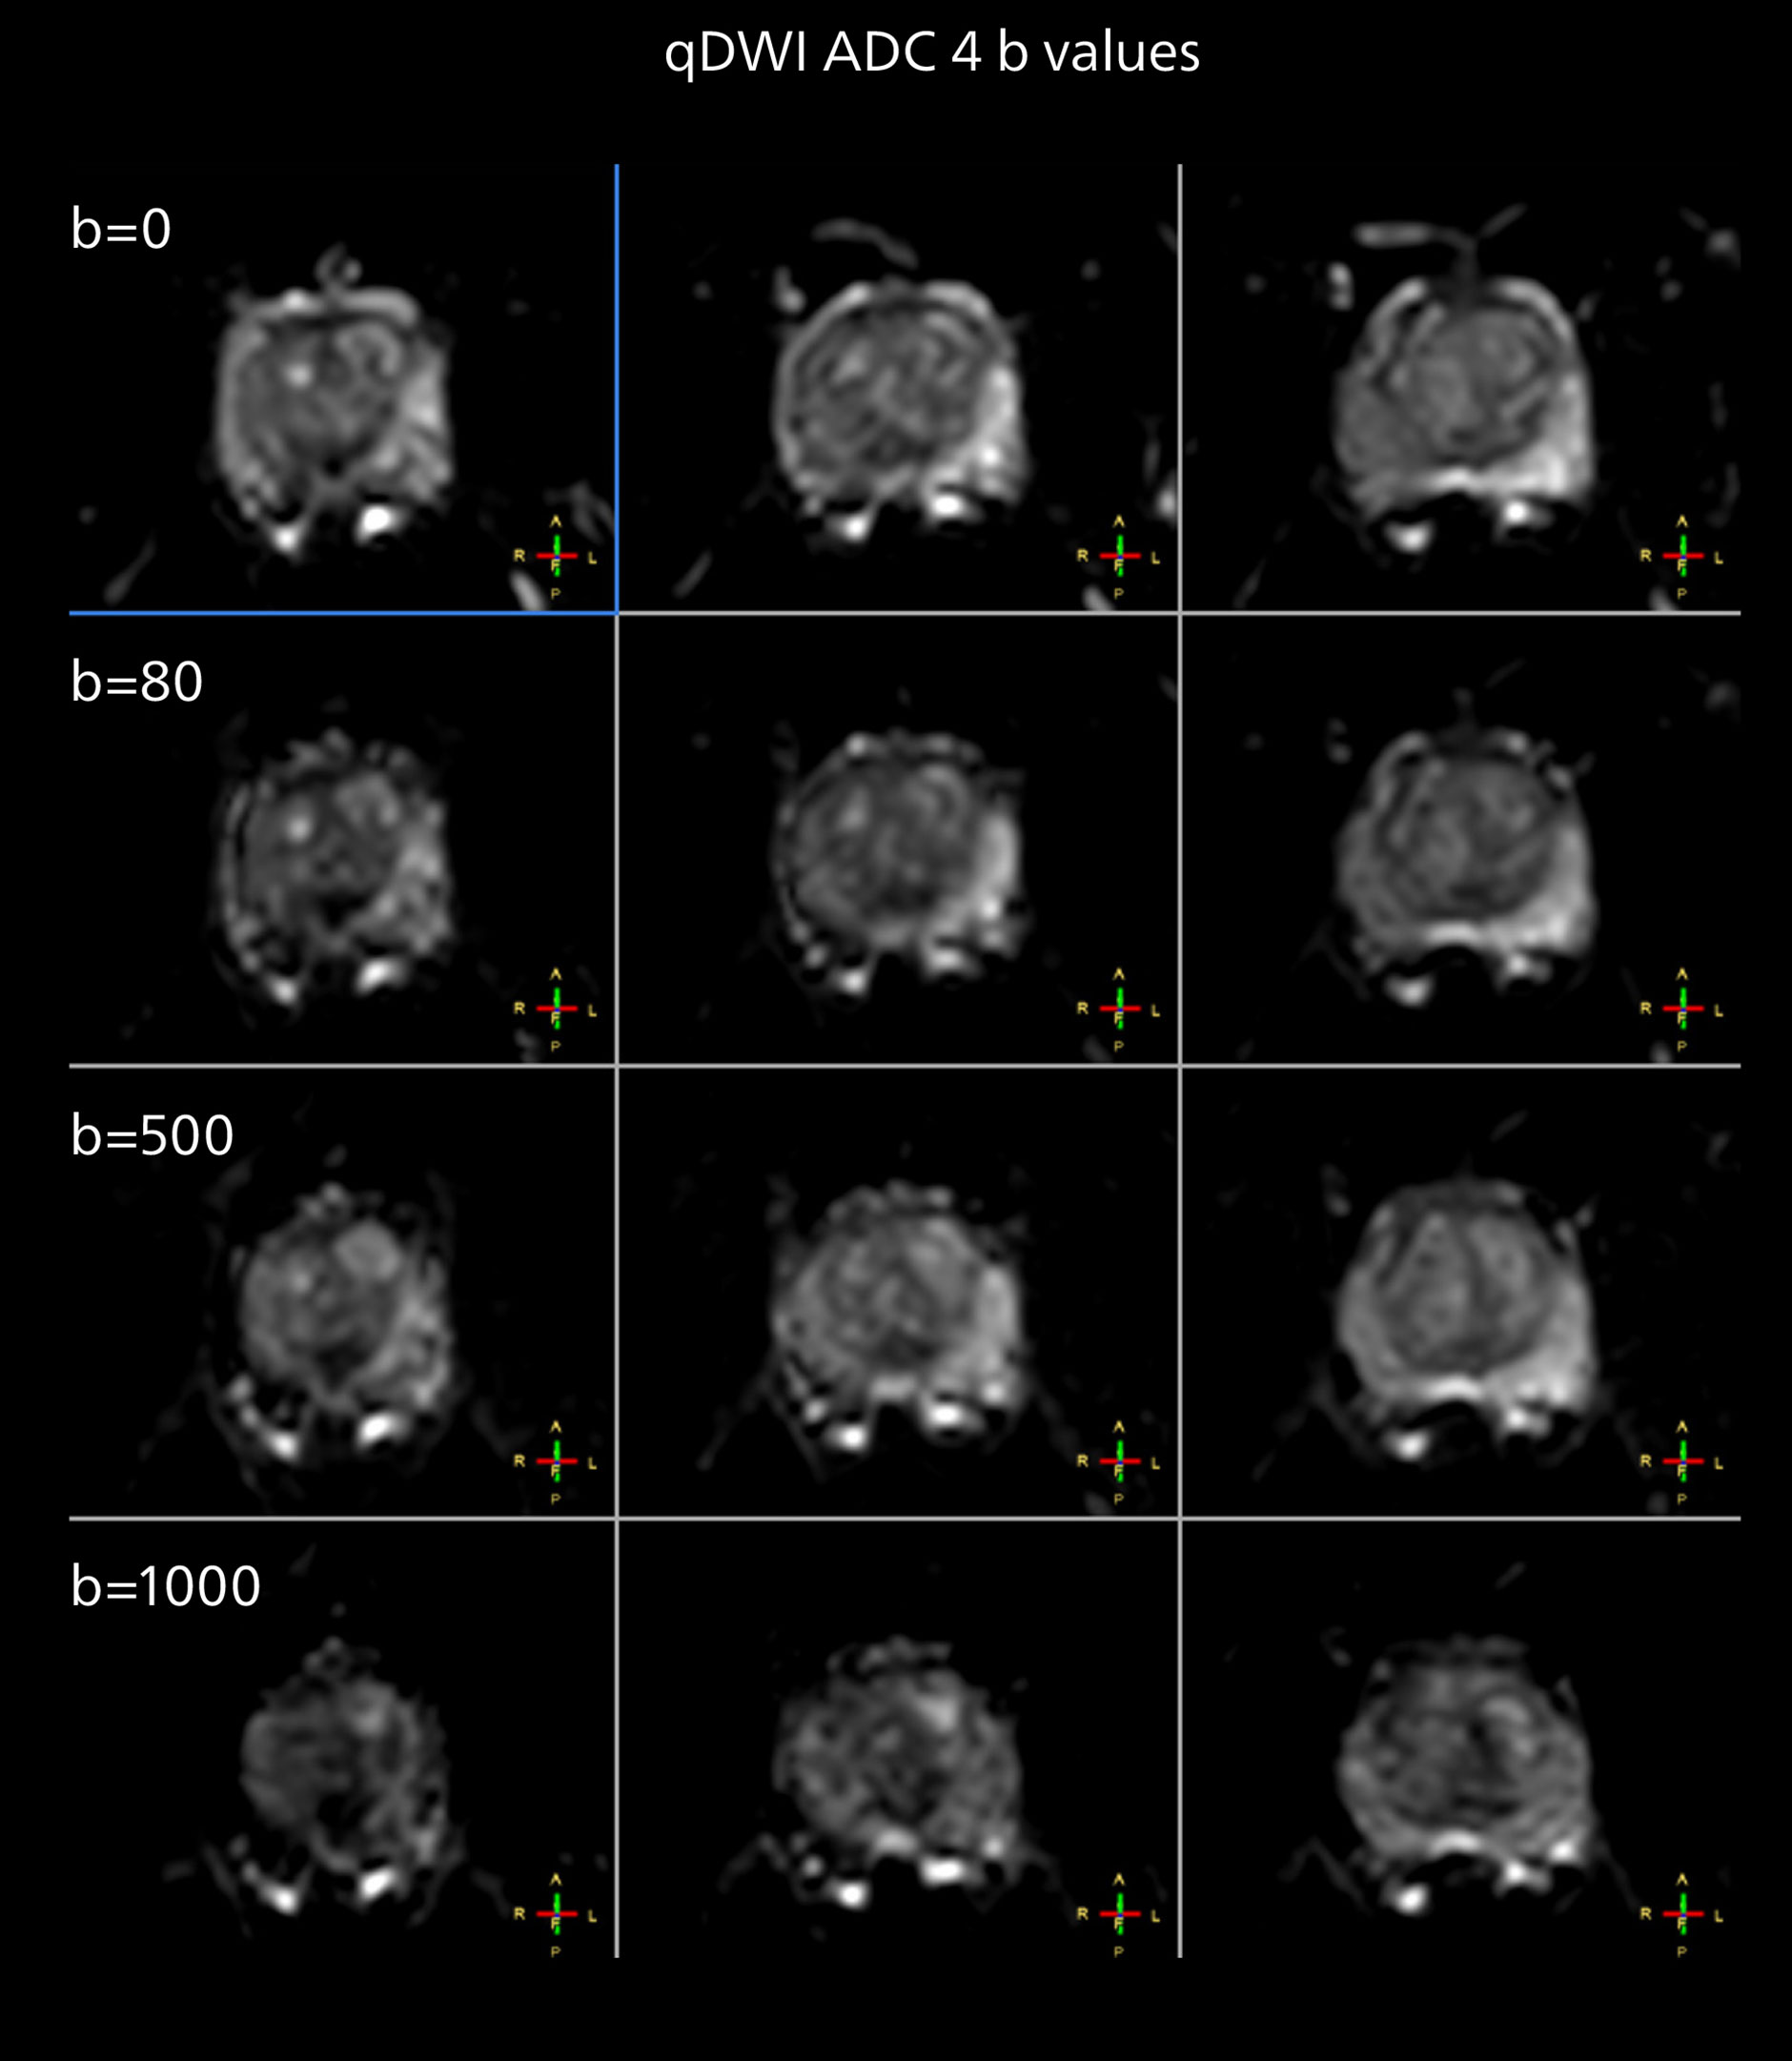

The examples on the left show the regular clinical diffusion protocol with four b-values up to b1000 s/mm². On the right, the T2W image shows a hypointense lesion that has low ADC and is clearly visible in b1400 and b2000 diffusion images, suggesting malignancy.

“We expect that the more powerful gradient system will allow improved diffusion results, meaning more directions and/or more shells [i.e. b-values] and higher SNR without lengthening examination times,” he says. “We also are confident that the Compressed SENSE and MultiBand SENSE acceleration methods will help here. For example, we plan to investigate, whether diffusion techniques in body imaging may serve as an alternative to contrast agent application.”

“From our experience, the diffusion imaging (DWI) seems to provide the most useful information in this process. And it is exactly the diffusion imaging that benefits much from the powerful MR 7700 gradients. So, we will investigate how even higher resolution DWI may enable an innovative approach in this area. The team also aims to investigate multiparametric imaging in combination with machine learning.”

The prostate DWI done so far with the MR 7700 looks promising; the quality of visualizing the gland and the areas of disease seems significantly improved. “In one of our first prostate patients we were already able to acquire a quite high-resolution diffusion image – using a b-value of 3000 – that clearly delineated the prostate lesion. That was a very nice example of what the MR 7700 gradients can achieve,” he says.